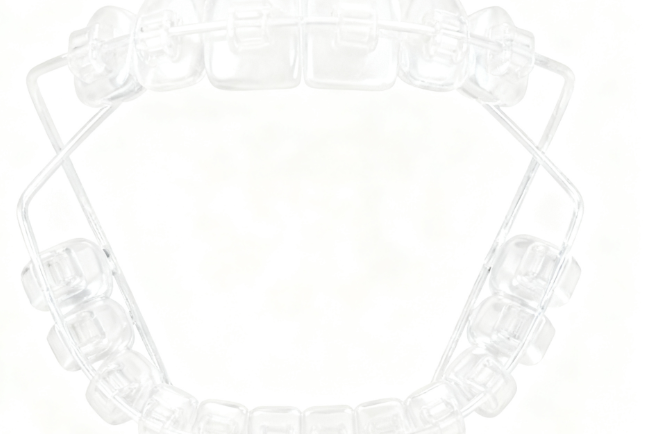

- 6、仙桃儿童早期干预矫正(如MRC肌功能矫治)价格:3000-15000元